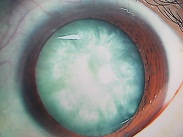

今日いらした24歳女性の症例です。

強い充血を認めます。写真の右側は、はやり目に特徴的な後遺症で、黒目(角膜)が濁っている写真です。もう少し分かりやすい、ヒドイ症例の写真を出したいのですが、ヒドイ症例は第一診察室には入らないようにしていただいたり、写真をとるなどの、余分な時間を少しでも省いて診療を行い、院内感染を予防する必要があり、なかなか難しいのです。